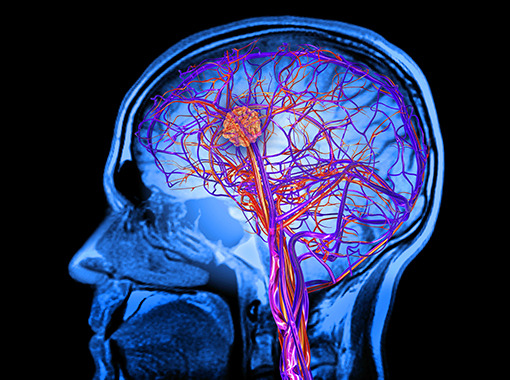

뇌 동정맥 기형(AVM)은 뇌의 동맥과 정맥이 비정상적으로 연결되어 혈류의 이상을 초래하는 선천성 질환입니다. 이러한 기형은 뇌출혈의 주요 원인 중 하나로, 조기에 발견하고 적절한 치료를 받지 않으면 심각한 신경학적 손상이나 생명 위협을 초래할 수 있습니다. 건강보험공단에서는 이러한 중증 뇌혈관질환 환자들을 위해 산정특례 제도를 통해 의료비 부담을 경감할 수 있는 혜택을 제공하고 있습니다. 이번 글에서는 뇌 동정맥 기형으로 인한 뇌출혈, 수술적 치료 방법, 그리고 산정특례 제도의 적용에 대해 자세히 알아보겠습니다.

뇌 동정맥 기형은 혈관벽이 약해져 있어 출혈의 위험이 높습니다. 특히, 다음과 같은 증상이 나타날 수 있습니다: